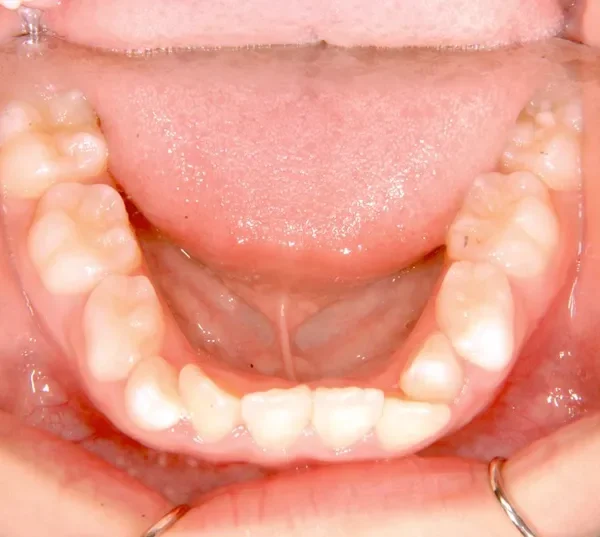

初診時年齢 小学校3年生 (女性) 主訴 出っ歯・前歯がゆがんでいる

診断名 叢生・上顎前突 装置名

状態 永久歯が生える隙間がない(叢生)

ガタガタ・でこぼこに生えている(叢生)

出っ歯(口元が出ている/上顎前突)

出っ歯と前歯のゆがみを主訴に来院されました。

低学年時は取り外しの装置を使用し、高学年になってからは見えにくい固定式の装置を使用して治療しました。

治療回数48回、7年2ヶ月の治療期間で矯正治療を終了しました。

主訴が改善され、ご満足頂きました。